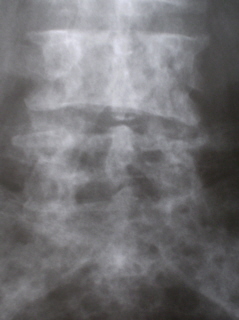

Иллюстрации 9, 10, 11. Множественные очаги деструкции костной ткани в поясничных позвонках и в крестце

Иллюстрации 12, 13, 14. Остеопоротическая трансформация костной ткани грудных позвонков с формированием патологического гиперкифоза, в результате клиновидной деформации тел позвонков и их уплощения (патологические переломы). Множественные очаги деструкции костной ткани округлой формы, без четких контуров.

Иллюстрации 15, 16. Аналогичные изменения в поясничных позвонках.